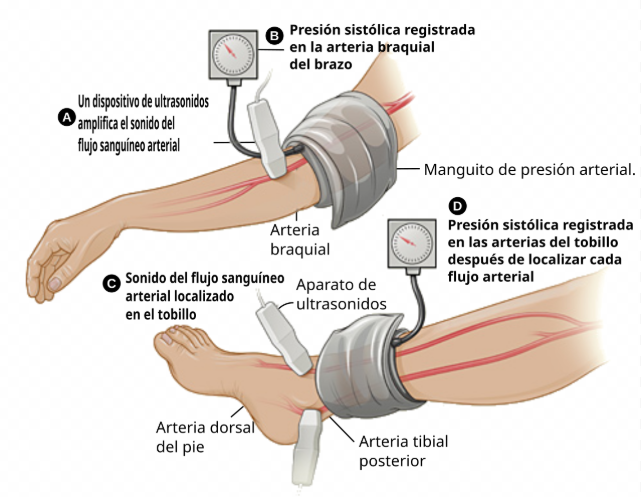

ÍNDICE TOBILLO-BRAZO (ITB) El Índice Tobillo-Brazo (ITB) es una prueba no invasiva, sencilla y muy útil en la práctica clínica para evaluar la presencia de enfermedad arterial periférica (EAP). ¿PARA QUÉ SIRVE EL ITB? Diagnóstico de enfermedad arterial periférica Es...